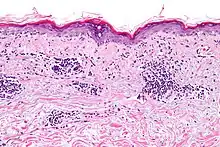

Vacuolar interface dermatitis, with lymphocytes in the dermis and epidermis (black arrow indicates one), and vacuolization (white arrow) at the dermoepidermal junction.

Vacuolar interface dermatitis (VAC, also known as liquefaction degeneration, vacuolar alteration or hydropic degeneration) is a dermatitis with vacuolization at the dermoepidermal junction, with lymphocytic inflammation at the epidermis and dermis.[1]